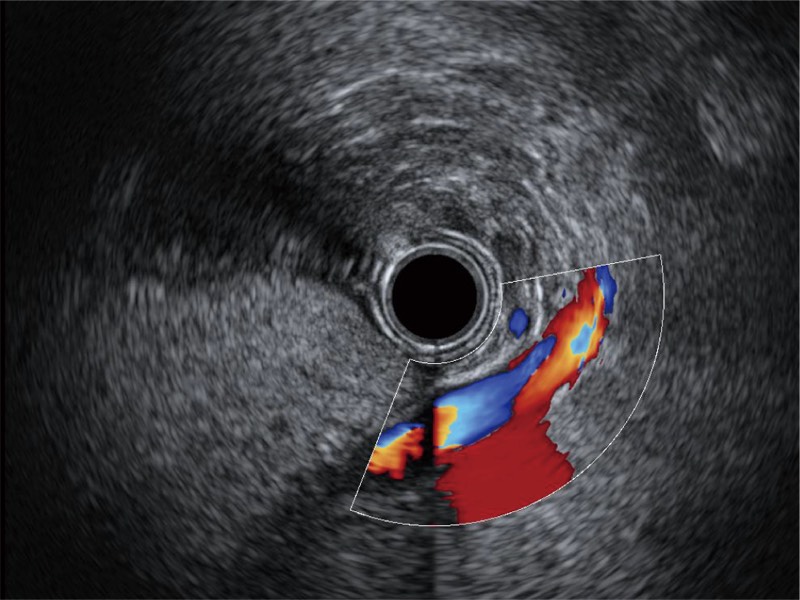

• 非线性融合造影

融合谐波技术

动态声压控制技术

TIC时间强度分析曲线

具有四种造影成像效果